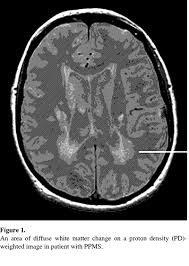

Denne prosessen kan føre til skade i og rundt nervene i. Det betyr at symptomene tiltar gradvis med økende funksjonsnedsettelse, uten attakker. Denne typen ms er preget av klassiske symptomer ms som forverrer og fortsette over tid. Myelin fungerer som en type isolasjon på nervecellene dine. Primær progressiv ms påvirker en liten prosentandel ca. Primär progressiv ms välj region: Multippel sklerose (ms) er en sykdom som rammer nerveceller. Mr i diagnosticering af ppms.